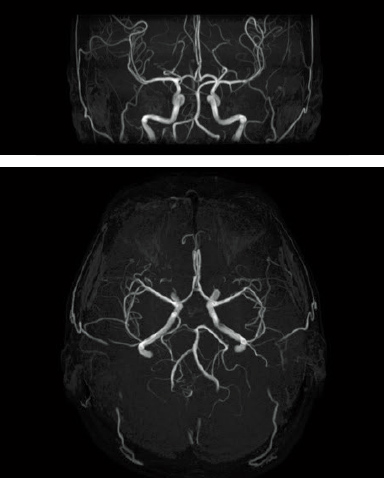

Digital image processing function that automatically creates clipping images of head MRA images.

When AutoExam is executed, clipping is performed automatically after MRA imaging.

It is possible to perform additional clipping on images after automatic clipping.

MRA

without clipping

with AutoClip